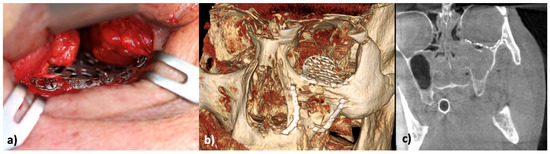

Also, the surgical intervention was performed like in case 1 with primary fixation of the drill guides on the medial and lateral buttresses via an intraoral approach and pre-drilling the screw holes. After guide removal open reduction and fixation of the mini plates was performed in accordance with the plan. Afterwards the infraorbital rim was stabilized by the third mini-plate and orbital floor was reconstructed with the orbital implant via a transconjunctival approach (Figure 9a–e).

Figure 9. (a) Intraoperative view of CAD/CAM surgical guides and drilling (1′ and 2′). (b) Pre-drilled holes after removal of surgical guides and before repositioning. (c) Insertion of CAD/CADM plates after repositioning of the zygomatic fracture (2). (d) Inserted and fixed CAD/CAM implants (1 and 2). (e) View of the infraorbital rim and fixed orbital wall implant.